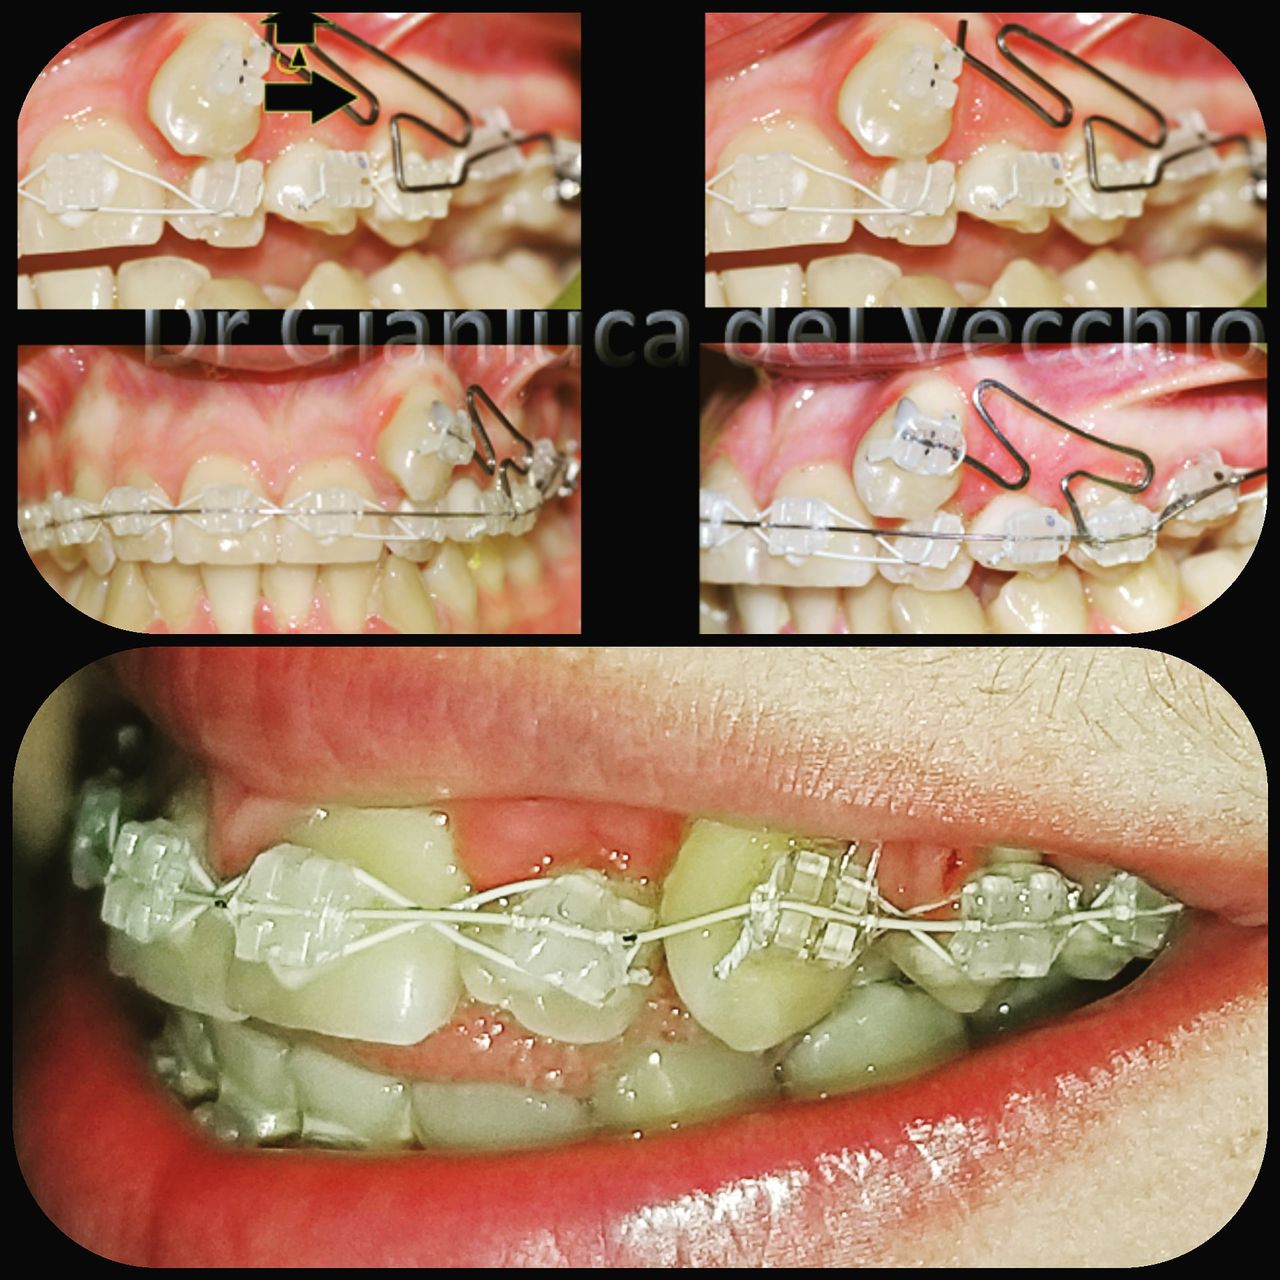

Il dottore ha acquisito una concezione quanto più pratica e moderna della disciplina e utilizza apparecchietti di diversi colori di tipo mobile e fisso, ma anche terapie sia estetiche che invisibili, fiore all’occhiello di poche realtà in Italia. Per terapie estetiche e invisibili si intendono quelle in grado di spostare i denti, senza che traspaia nulla dalla bocca o con stelline e fili bianchi, esattamente come i denti del paziente.

Ma ancora di più l’équipe è in grado di offrire un servizio davvero unico: la tecnica dei retainer attivi. Questa consiste in fili o bottoni che si incollano dietro i denti e che, quindi, nascondono completamente la terapia. Questo tipo di prestazioni aiuta a superare la grande difficoltà psicologica, che spesso si insinua anche negli adulti, di dover spostare i propri denti per un sorriso perfetto: si consideri che tale difficoltà non viene affrontata, il più delle volte, proprio per l’imbarazzo che una apparecchiatura ortodontica genera in chi la usa. Queste tecniche, insieme alle mascherine invisalign invisibili di cui è provider ufficiale e agli attacchi in ceramica, sono tutte quotidianamente utilizzate presso i nostri reparti, in cui è possibile associarle in un discorso multidisciplinare a tutte le altre esigenze della odontoiatria classica.